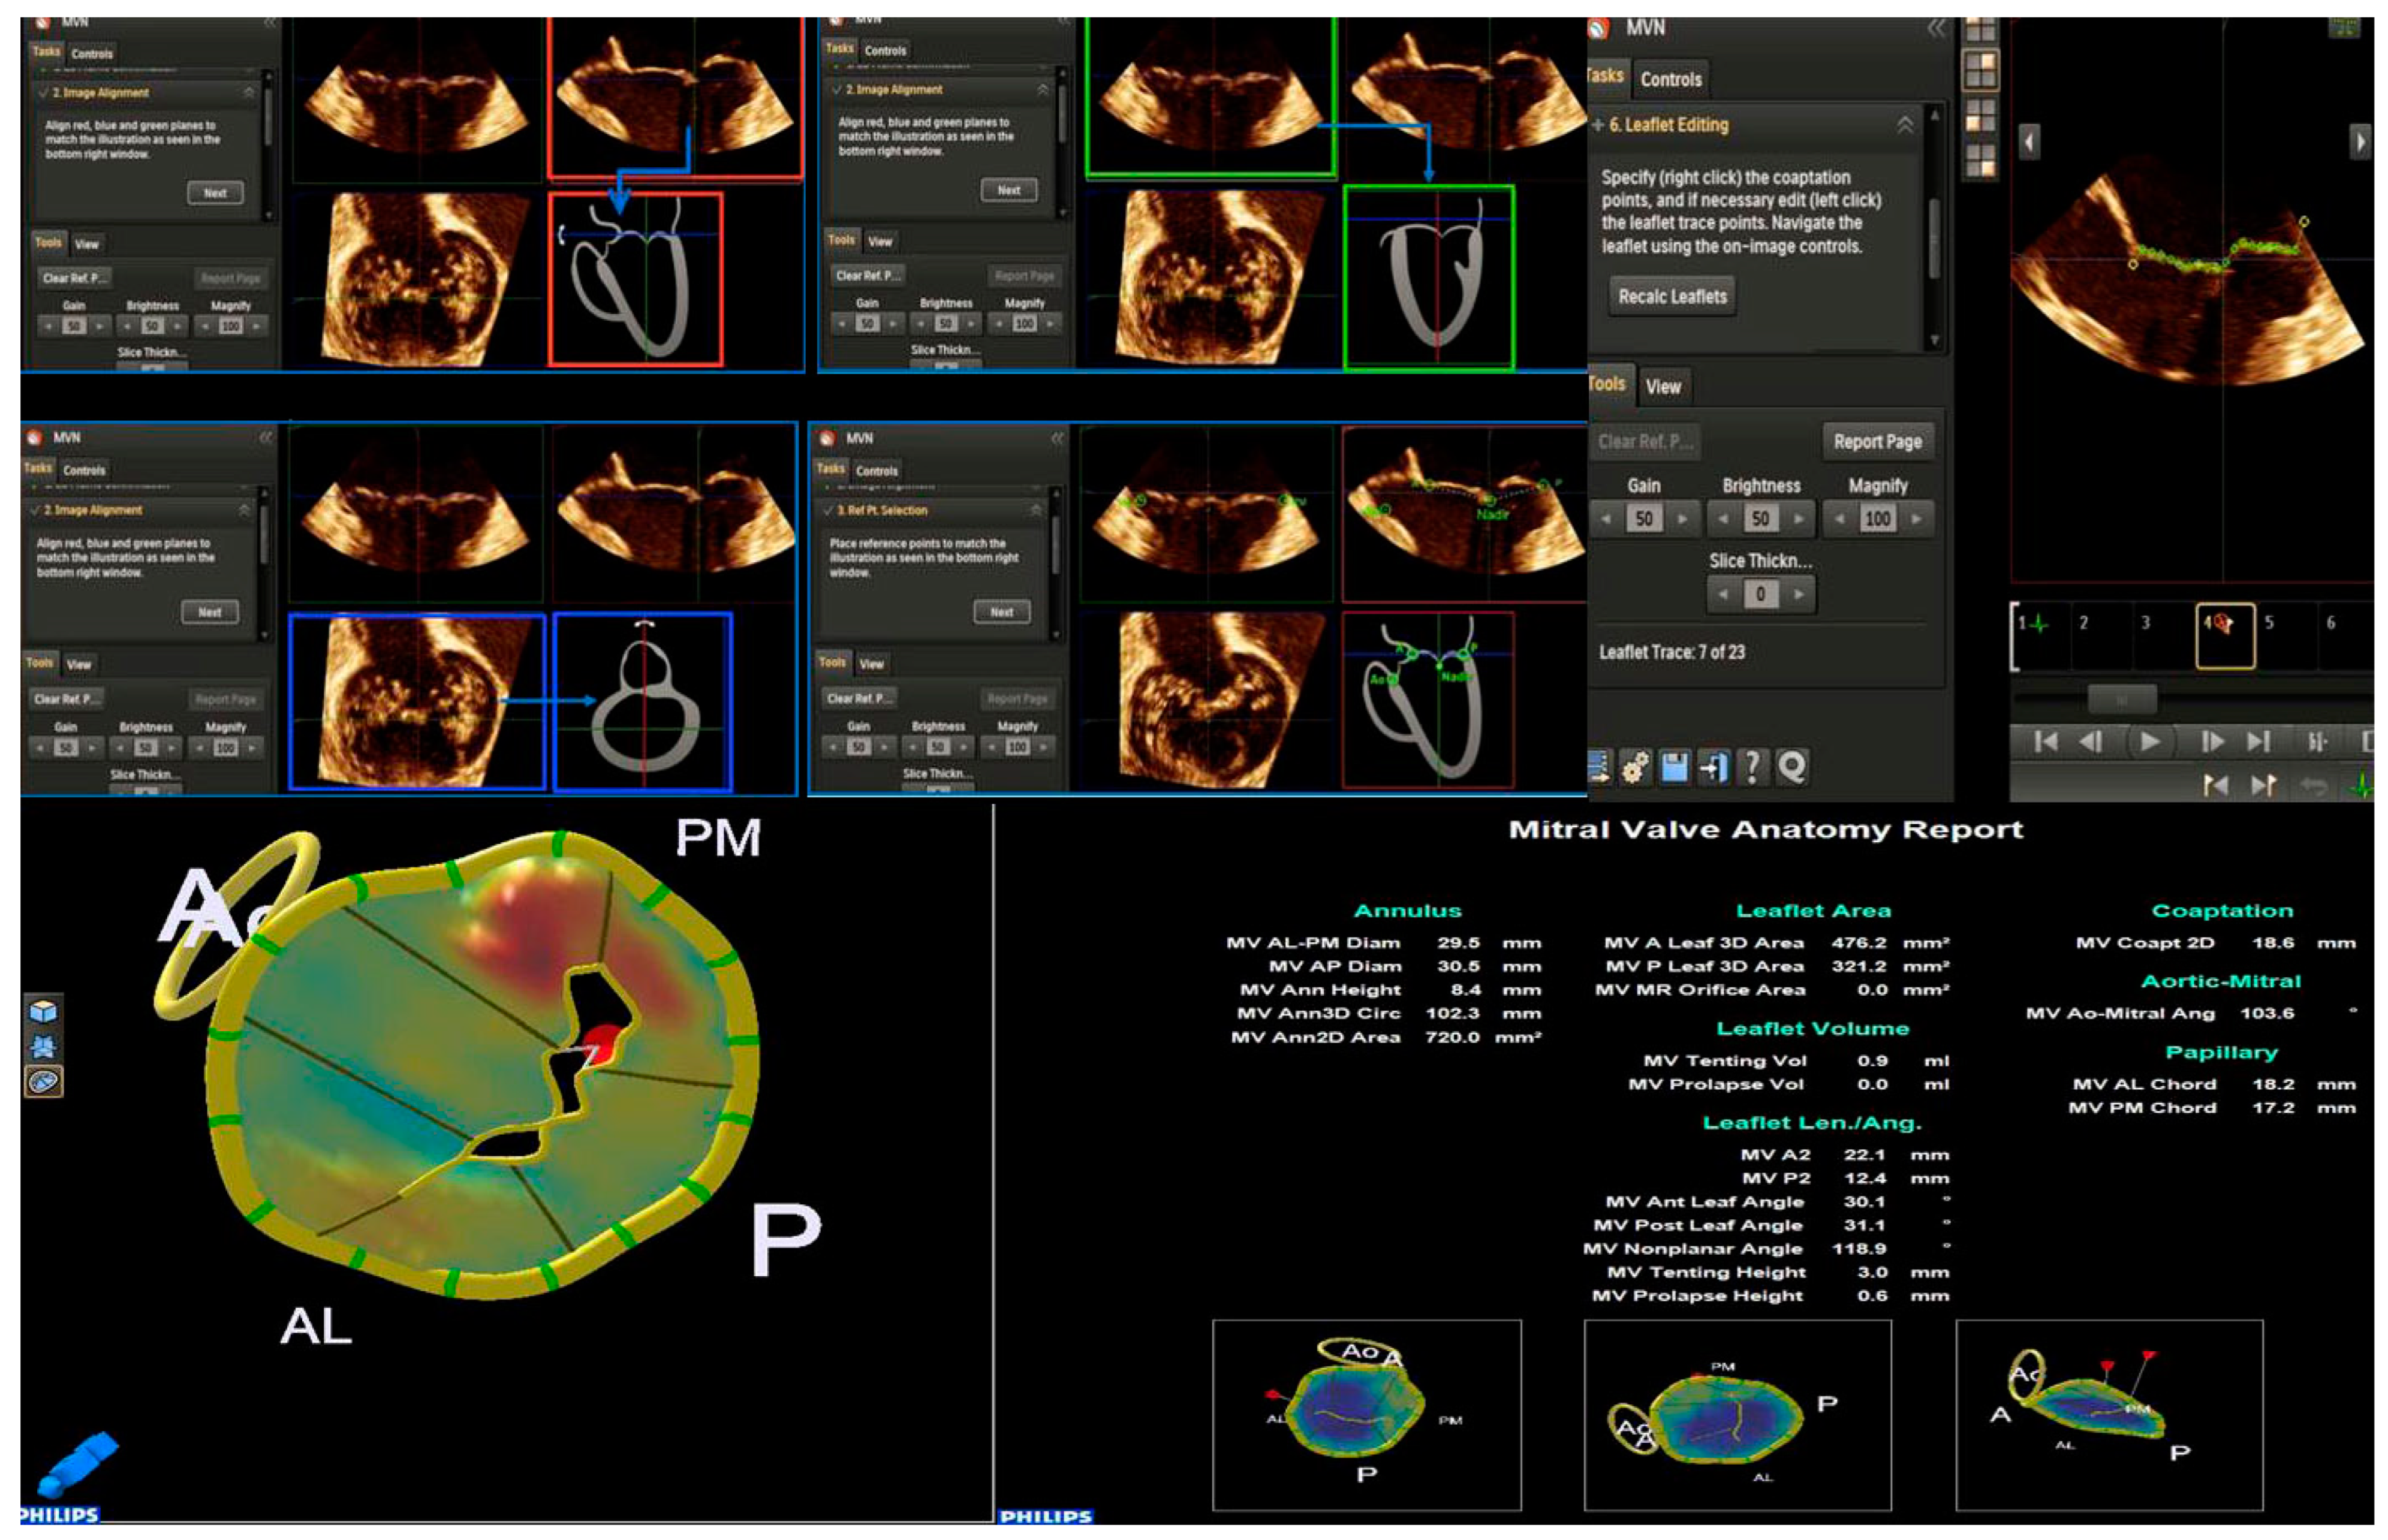

2.2. Mitral Valve Quantification (MVQ) and Mitral Valve Navigation (MVN)